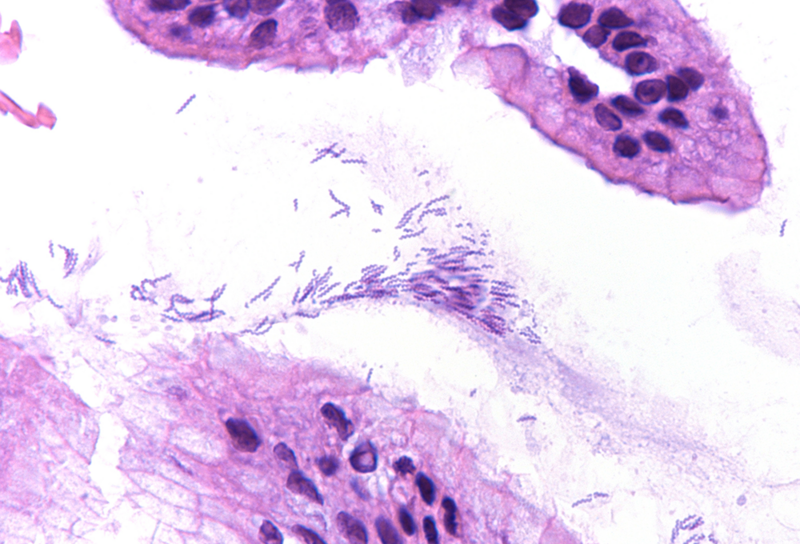

Histologic examination showed moderate chronic antrum gastritis with mild focal neutrophilic inflammation and small superficial mucosal erosions (Panel A). In the mucus layer close to the surface epithelium and in several of the foveolar pits, large, thin, corkscrew-shaped bacilli were found (Panel B) that could be highlighted with a H. pylori immunostain (Panels C-D). The characteristic morphology of the bacterial structures and their cross-reactivity with the anti-H. pylori antibody were consistent with Helicobacter heilmannii.